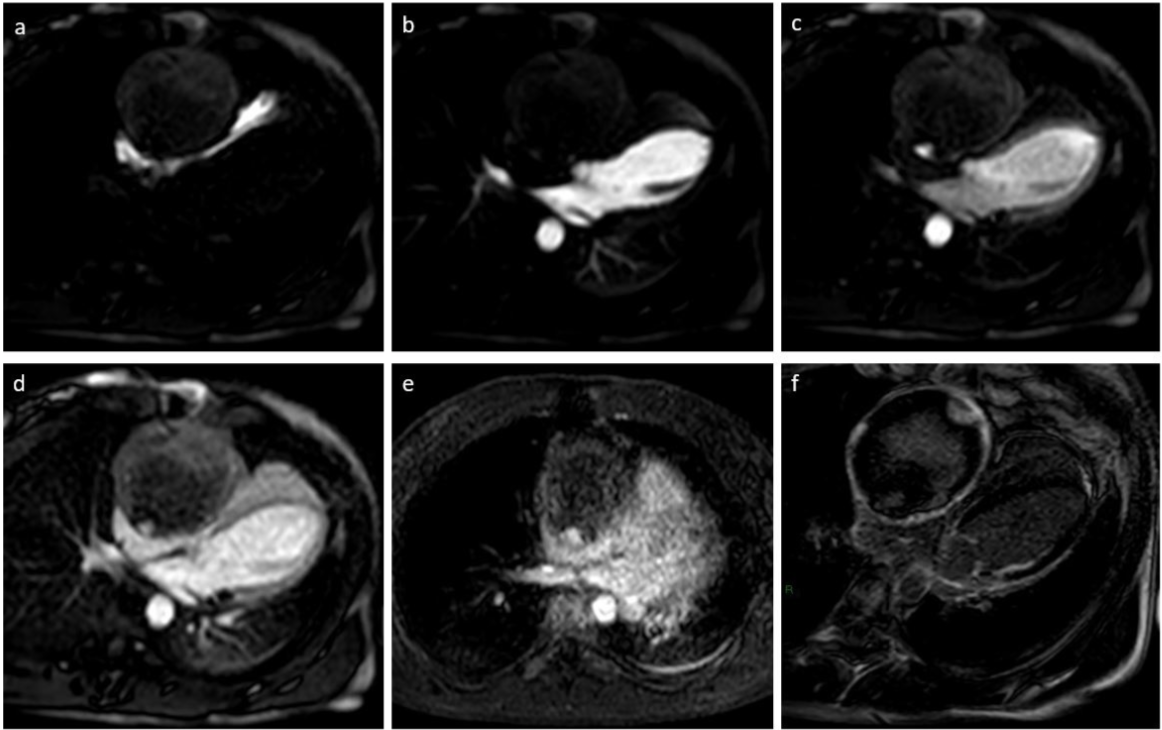

(a) to (d) first pass rest perfusion images show no enhancement of the lesion in the RV (a) and LV (b) cavity phases. Just after the LV phase (c) a focal area of enhancement can be seen along the posterior wall, persisting into the myocardial phase (d); the same area can be seen in FSPGR T1W post-contrast (e) and delayed enhancement (f) images. Ischemic LGE along the basal lateral wall of the left ventricle, extending into the medium infero-lateral wall is also observed.